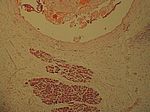

Chron. skleros. kalz. Pankreatitis, HE